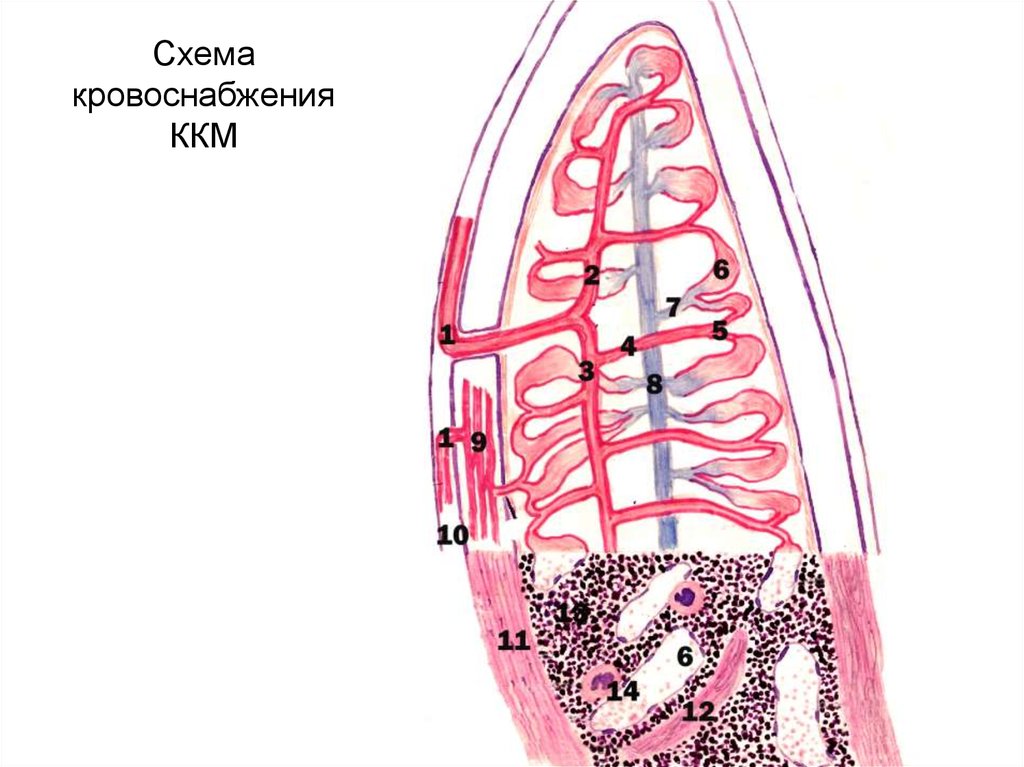

Изучение костного мозга: анатомия и функции